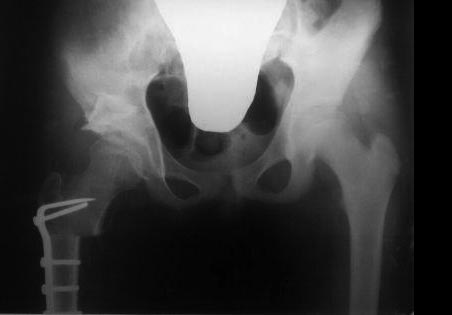

У нас реконструкция крыши делается по типу создание навеса (методика

УзНИИТО) в зависимости от недоразвития части крыши, ну чаще

передневерхней, сначала открываем сустав, ревизия, удаление

внутрисуставных тел, проверка хрящевой  губы, определение размера

недопокрытия головки,  дугообразная остеотомия крыши  по краю

прикрепления капсулы сустава к кости, параллельно стенки вертлужной

впадины до внутреннего кортикала , формируем крышу, после  устранение

торсии, вальгуса шейки и определяется размер укорочения, взятый

трансплантат внедряется в паз над крышей, примерно так.. То, что попало

в руки сейчас, примеры операции у пациентки 13лет, и результат у 12 лет,

до снимков не нашел, если найду еще отправлю.